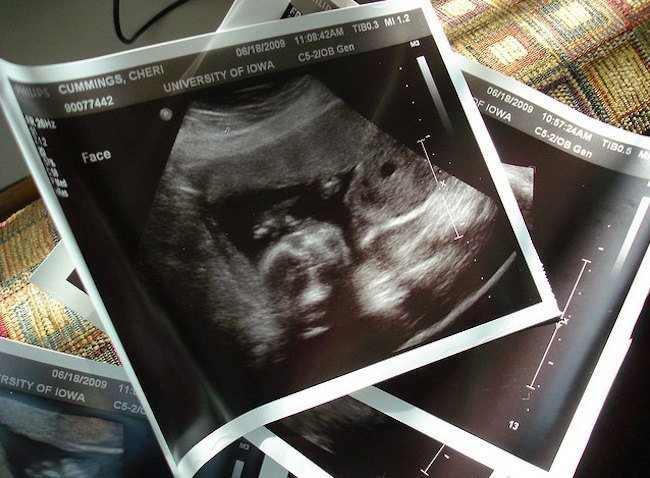

La primera ecografía: ¿Mejor a partir de las 12 semanas?

En la seguridad social la primera ecografía es a las doce semanas, cuando se cumple el primer trimestre, que puede parecer un poco tarde porque hasta los tres meses nadie ve cómo va el niño, pero que en el fondo responde, creo, a una realidad: algunos embarazos se pierden irremediablemente o bien puedes llevarte algún que otro susto.

Según cuándo se realice la primera ecografía pueden llegar a verse cosas que después no se verán (dos embriones, por ejemplo, que a las doce semanas es sólo uno) y pueden no verse cosas que después sí se verán.

Con esto me refiero a que es posible que si la ecografía se hace demasiado pronto no se aprecie latido en el feto, sin ser ello muestra de que hay un problema. Quizás unos días después el latido se empieza a notar o quizás se trata de un feto cuyo corazón nunca llegará a latir.

Las sociedades profesionales ginecológicas recomiendan la primera ecografía a partir de la semana 12 desde la última regla. El motivo es principalmente evitar sufrimientos innecesarios, aunque de este modo muchos padres se quedan sin saber qué ha pasado en ese tiempo.

Foto | Stephen Cummings en Flickr